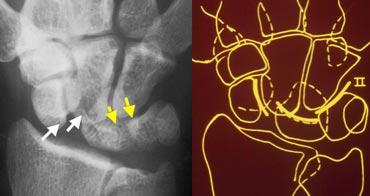

Phim X-quang cổ tay tư thế thẳng (PA) và hình minh họa sơ đồ cho thấy sự gián đoạn của cung cổ tay thứ nhất

Gián đoạn các cung cổ tay

Một cung được coi là gián đoạn khi không thể vẽ theo một đường cong trơn liên tục. Sự gián đoạn của một trong các cung cho thấy có gãy xương hoặc đứt dây chằng dẫn đến bán trật khớp hoặc trật khớp.

Ở hình bên trái, có thể nhận thấy sự gián đoạn của cung I tại khớp nguyệt-tháp.

Hình bên trái cho thấy sự gián đoạn của cung cổ tay thứ hai tại khớp thuyền-nguyệt và khớp nguyệt-tháp. Mặc dù có một khoảng hở ở cung thứ nhất, nhưng vẫn có thể vẽ theo một đường cong trơn liên tục, do đó cung I được coi là còn nguyên vẹn.